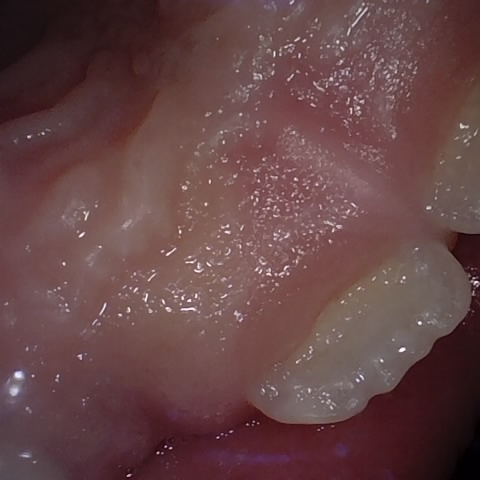

NHD39163

Annotated as "Good"

Original Image Rendering Image